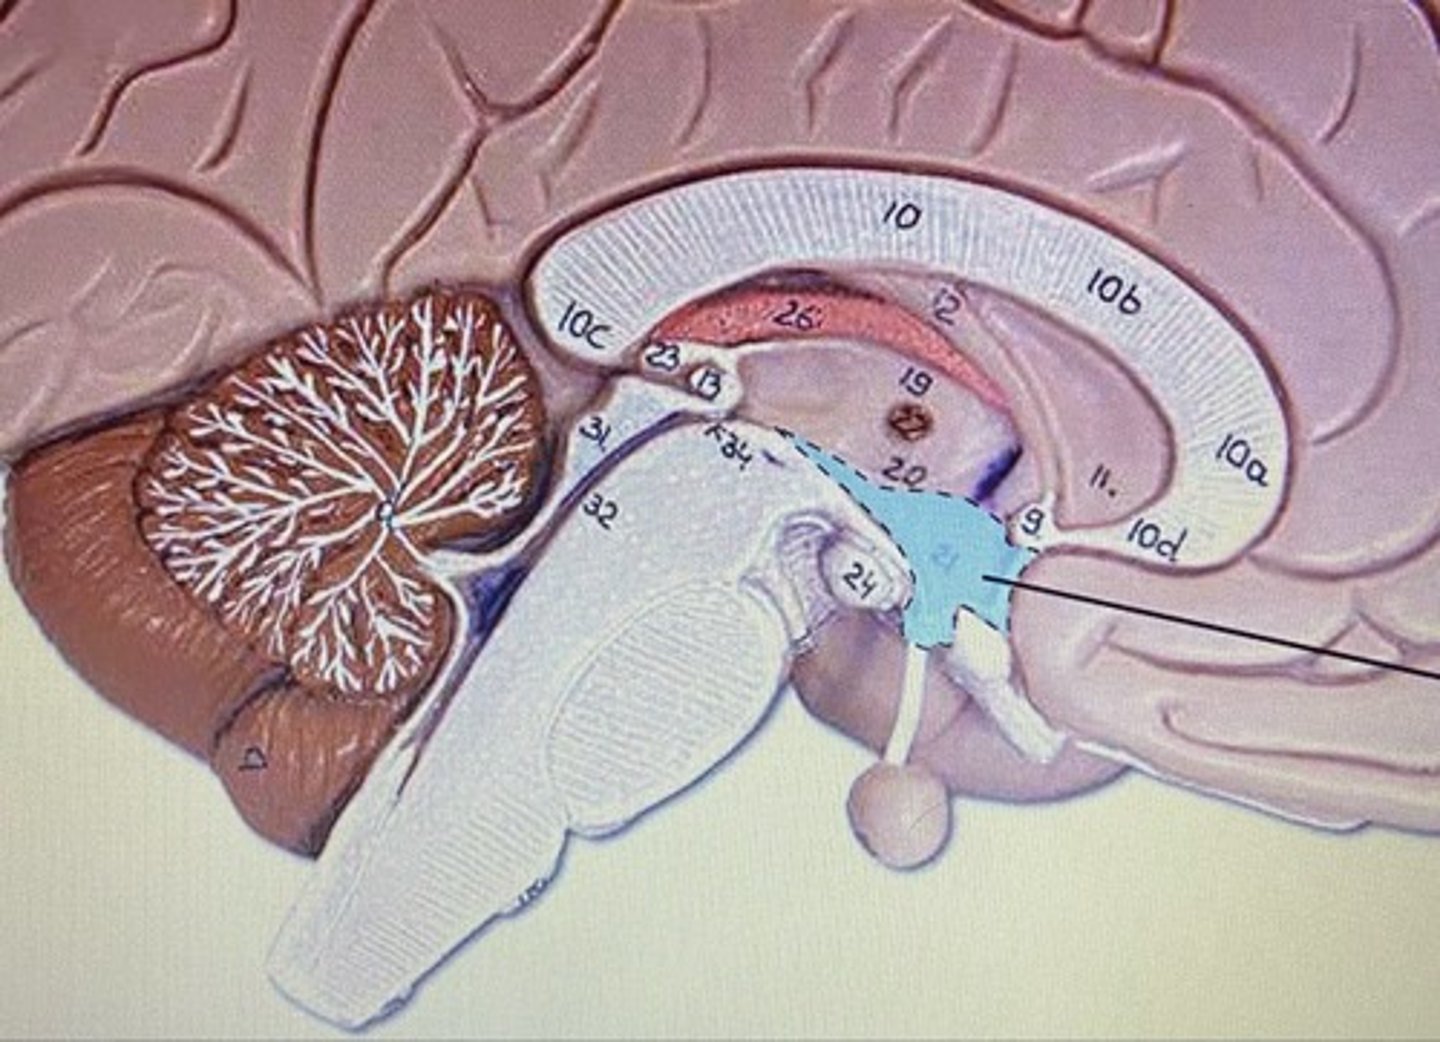

Cerebellum

Arbor Vitae

Medulla Oblongata

Infundibulum

Pituitary Gland

Superior Colliculus

Inferior Colliculus

Third Ventricle

Fourth Ventricle

Cerebral Aqueduct

Cerebellum

-coordinates muscles movements, muscle memory

Inferior Colliculi

-auditory reflexes

Superior Colliculi

-visual reflexes

Pineal Body

-controls sleep/wake cycles

Pons

-bridge that links medulla oblongata to thalamus

Medulla Oblongata

-houses autonomic centers